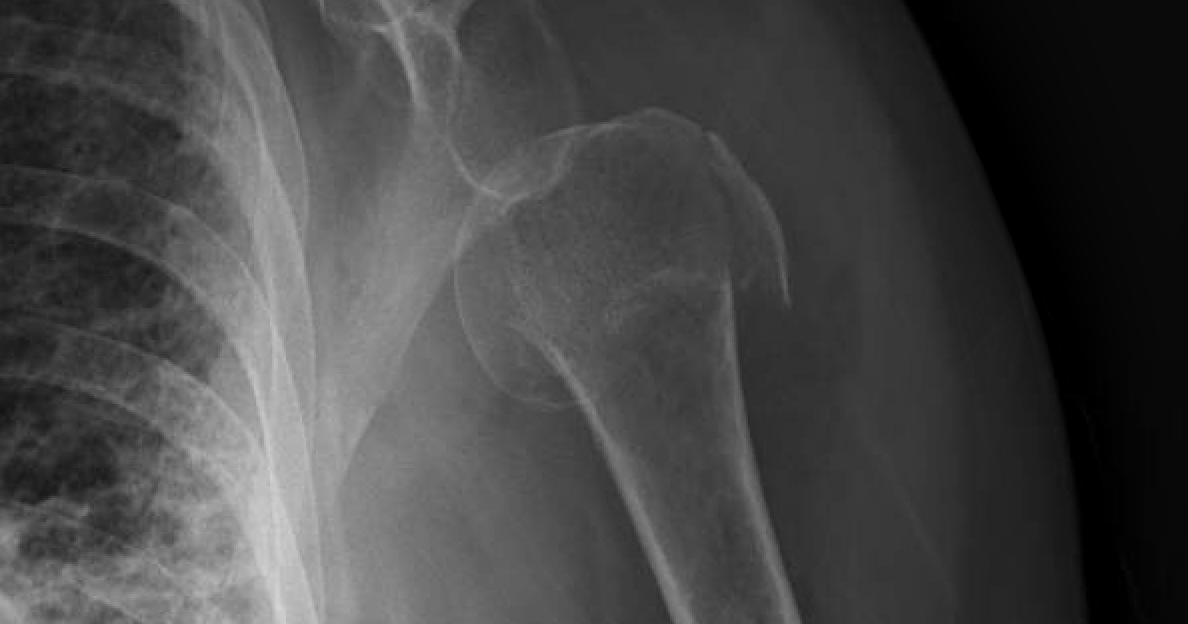

Shoulder and Elbow Surgery Shoulder subluxation after proximal humerus Shoulder Subluxation No Pain Describe the diagnostic approach for evaluating shoulder subluxation injuries. shoulder subluxation can cause pain and weakness in the shoulder and a feeling of instability or giving way in. a shoulder subluxation is a partial shoulder dislocation involving the ball of the upper arm bone (the humerus). What is shoulder subluxation and how is it treated? shoulder subluxation,. Shoulder Subluxation No Pain.

Shoulder and Elbow Surgery Shoulder subluxation after proximal humerus Shoulder Subluxation No Pain What is shoulder subluxation and how is it treated? shoulder subluxation happens when the ball of the upper arm bone comes partly out of its socket. Describe the diagnostic approach for evaluating shoulder subluxation injuries. a shoulder subluxation is a partial shoulder dislocation involving the ball of the upper arm bone (the humerus). in some people, a. Shoulder Subluxation No Pain.

Shoulder and Elbow Surgery Shoulder subluxation after proximal humerus Shoulder Subluxation No Pain It is more annoying, preventing. Describe the diagnostic approach for evaluating shoulder subluxation injuries. In this condition the humeral head slips out of the glenoid cavity as a result of weakness of rotator cuff or looseness of the glenohumeral ligaments. shoulder subluxation can cause pain and weakness in the shoulder and a feeling of instability or giving way in.. Shoulder Subluxation No Pain.

Shoulder and Elbow Surgery Shoulder subluxation after proximal humerus Shoulder Subluxation No Pain shoulder subluxation, a subset of shoulder instability, occurs when the shoulder joint partially dislocates. What is shoulder subluxation and how is it treated? a shoulder subluxation is a partial shoulder dislocation involving the ball of the upper arm bone (the humerus). Describe the diagnostic approach for evaluating shoulder subluxation injuries. It is more annoying, preventing. in some. Shoulder Subluxation No Pain.